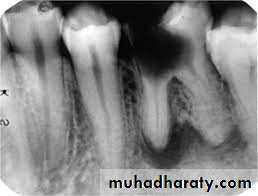

Under normal conditions, the pulpodentin complex is sterile and isolated from oral microbiota by overlying enamel, dentin and cementum.Whenever dentin is exposed, the pulp is put at risk of infection as a consequence of the permeability of normal dentin

dictated by its tubular structure

In the event that the integrity of these natural layers is breached (e.g., as a result of caries, trauma-induced fractures and cracks, restorative procedures, scaling and root planning, attrition, abrasion) or naturally absent (e.g., because

of gaps in the cemental coating at the cervical root surface) the pulpodentin complex is exposed to the oral environment .

Dentinal tubules traverse the entire width of the dentin and have a conical conformation, with the largest diameter located near the pulp (mean, 2.5 µm) and the smallest diameter in the periphery, near the enamel or cementum (mean, 0.9 µm) The smallest tubule diameter is entirely compatible with the cell diameter of most oral bacterial species, which usually ranges from 0.2 to 0.7 µm.

it has been demonstrated that bacterial invasion of dentinal tubules occurs more rapidly with a non vital

pulp than with a vital pulp

• With a vital pulp, outward movement of dentinal fluid and the tubular contents (including odontoblast processes, collagen fibrils, and the sheath like lamina limitans that lines the tubules) influence dentinal permeability and can conceivably delay intratubular invasion by bacteria.

As long as the pulp is vital, dentinal exposure does not represent a significant route of pulpal infection, except when dentin thickness is considerably reduced or when the dentin permeability is significantly Increased Most of the bacteria in the carious process are non motile; they invade dentin by repeated cell division, which pushes cells into tubules. Bacterial cells may also be forced into tubules by hydrostatic pressures developed on dentin during mastication.

Bacteria inside tubules under a deep carious lesion can reach the pulp even before frank pulpal exposure. As mentioned, it has been assumed that the pulp will not be infected if it is still vital. The few bacteria that reach the pulp may not

be significant, because the vital pulp can eliminate such a transient infection and rapidly clear or remove bacterial products.

On the other hand, if the vitality of the pulp is compromised and the defense mechanisms are impaired, even a small amount of bacteria may initiate infection.

Direct exposure of the dental pulp to the oral cavity is the most obvious route of endodontic infection. Caries is the most common cause of pulp exposure, but bacteria may also reach the pulp via direct pulp exposure as a result of iatrogenic restorative procedures or trauma